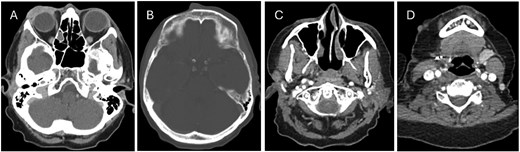

CT head showing (A) right periorbital mass, (B) anterior soft tissue lesion along the forehead medial to the site of prior frontal bone decortication, (C + D) nodal and dermal metastatic deposits within the right neck.